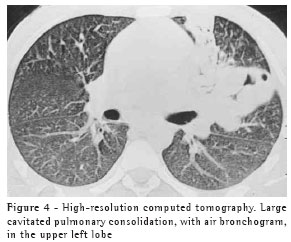

The most frequent finding in the imaging, present in the seven patients, was ill-defined consolidation (Figures 1, 2, 3 and 4). Five of patients presented air bronchogram, principally at the periphery of the lesion. In three cases, the consolidation was organized in the form of a mass. In six of the seven patients, irregular areas of cavitation were observed within the consolidations. Multiple cavitations were seen in five patients, and a singular cavitation was observed in one patient. In the patient presenting no cavitation, there were hypodense areas suggestive of necrosis (Figure 5). Only one of the patients presented air-fluid levels within the cavities.

Cavitated lesions predominated in the upper lobes, four in the right lobe and one in the left lobe. In one patient, the middle lobe was also affected. In two cases, such lesions occurred in the lower lobes, one in the right lobe and one in the left lobe. In four cases, the lesions affected only the lobes mentioned above and were therefore unilateral. In the remaining three cases, the contralateral lung was also affected, albeit to a lesser degree. In one case, there was also relatively thin-walled, multiloculated cavitation, without an air-fluid level, in the middle lobe.

Small centrilobular nodular opacities presenting a 'tree-in-bud' pattern, predominantly encircling the area of consolidation, were observed in three patients. In one of those patients, the lesions were also found in the hanging portions of the lower lobes. Peribronchial nodules, tending toward confluence and located in the periphery of the pulmonary consolidations, were observed in four cases.

In our study, the principal pattern of pulmonary involvement was air bronchogram and cavitation, which was present in six patients. There were multiple cavitations in five cases and a singular cavitation in one. The consolidations were large and had irregular contours. The air bronchograms were located in the peripheral portions of the lesions. The pulmonary lobe most frequently involved was the upper right lobe, which was affected in four patients. Most of the case review studies confirm these findings.(2,5) Some studies have reported that, although cavitation might not be present at the time of diagnosis, it develops over the course of the disease.(4) In the sample evaluated in the present study, air-fluid levels within the cavitations were seen in only one patient.

Other findings were ground glass opacities, peribronchial nodules, small nodules of predominantly centrilobular distribution, and the "tree-in-bud" pattern. These alterations were predominantly seen surrounding the cavitated consolidations. In one case, they were also present in both of the lower lobes. It is believed that this finding indicates bronchogenic dissemination of the infection.